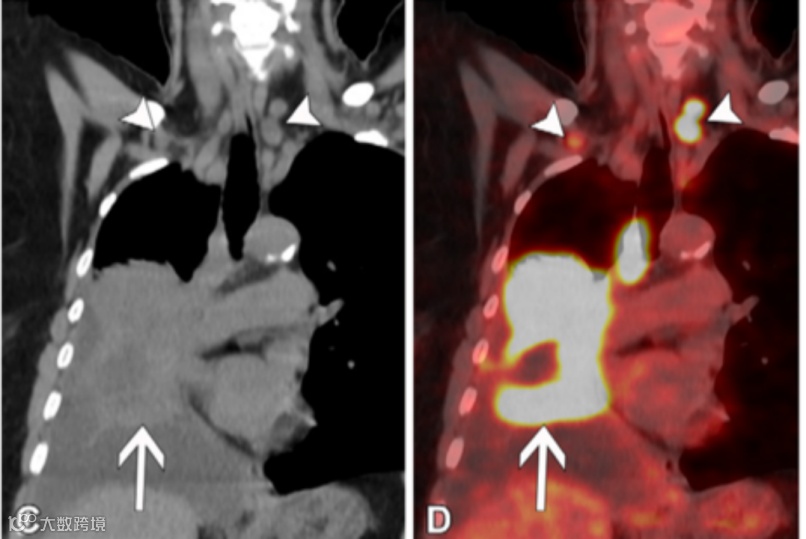

(C,D)58岁男性NSCLC患者的冠状重建未增强胸部CT图像(软组织窗)(C)显示右下叶原发肿瘤侵犯右肺门(箭头),并且在1R和1L站点发现转移性N3双侧低颈淋巴结(短箭头)。与C图像相同水平的冠状融合FDG PET/CT图像(D)显示这些淋巴结(短箭头)呈FDG高摄取,类似于原发肿瘤(箭头)。对于锁骨上淋巴结(1号站点)受累,无论是同侧还是对侧淋巴结受累,均视为N3期病变。